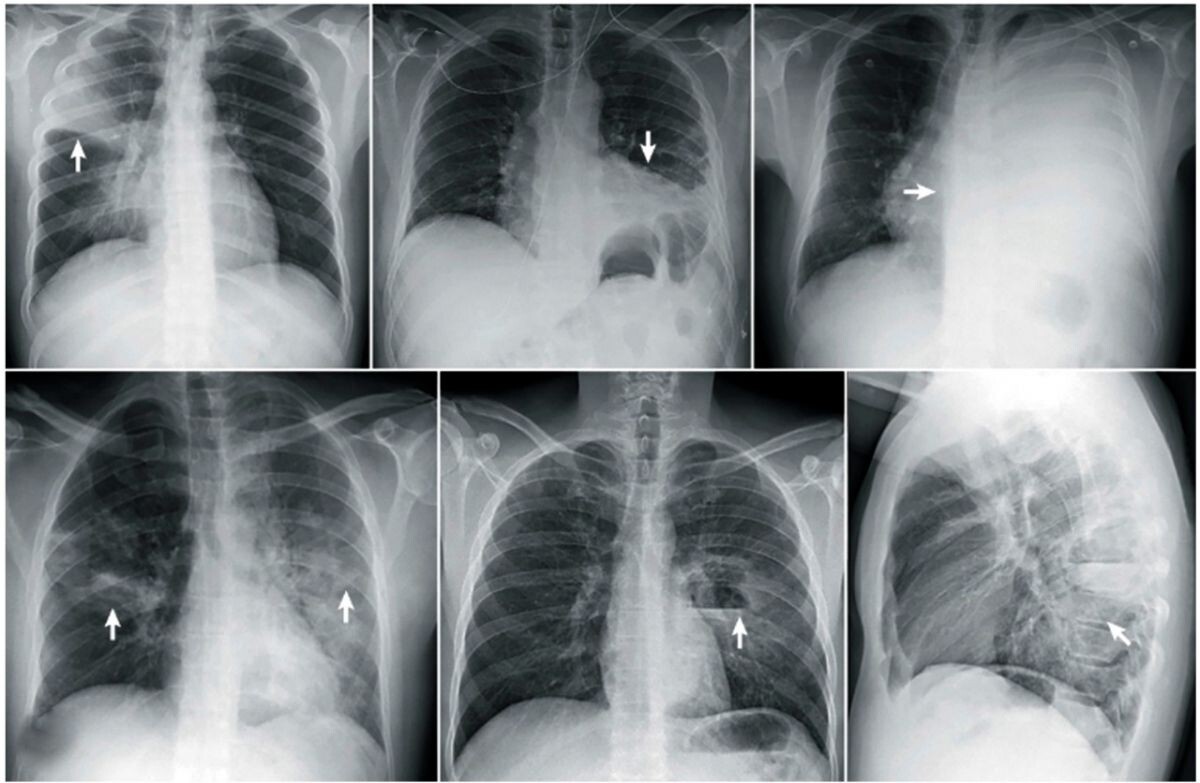

Пожилая рязанка обратилась в поликлинику номер 14 с жалобами на одышку. Во время осмотра терапевт заподозрила воспаление лёгких - при аускультации были слышны влажные мелкопузырчатые хрипы, которые могут свидетельствовать о скоплении мокроты в дыхательных путях.

Пациентку доставили в ОКБ бригадой скорой помощи. В ходе дополнительного обследования врачи выявили двустороннюю пневмонию средней степени тяжести с поражением лёгочной ткани до 60 процентов. Ситуацию осложняли сопутствующие заболевания, в том числе сахарный диабет второго типа.